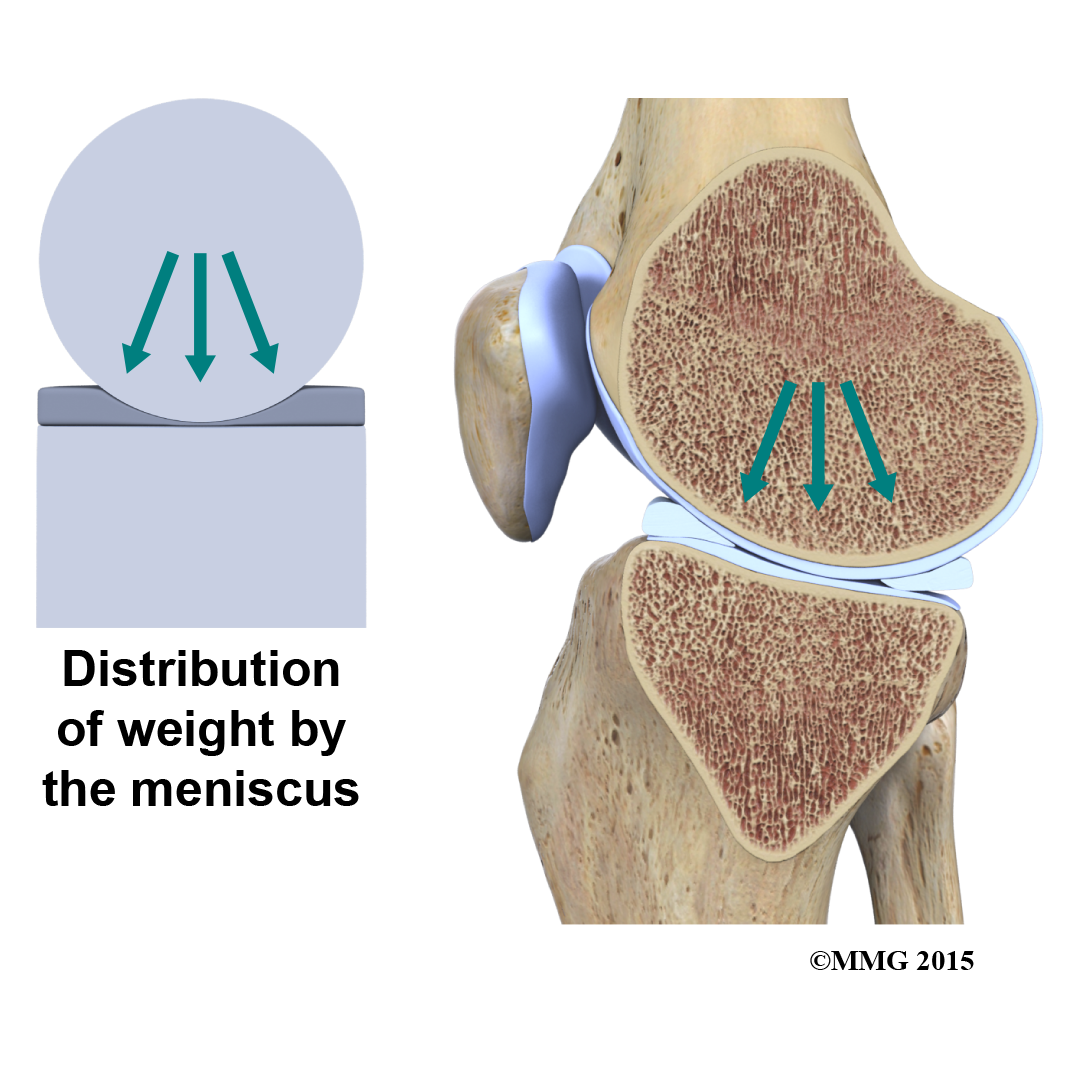

The two menisci of the knee are important for two reasons: (1) they work like a gasket to spread the force from the weight of the body over a larger area, and (2) they help the ligaments with stability of the knee.

The menisci act like a gasket, from the femur to the tibia.

Without the menisci, any weight on the femur will be concentrated to one point on the tibia. But with the menisci, weight is spread out across the tibial surface. Weight distribution by the menisci is important because it protects the articular cartilage on the ends of the bones from excessive forces. Without the menisci, the concentration of force into a small area on the articular cartilage can damage the surface, leading to degeneration over time.